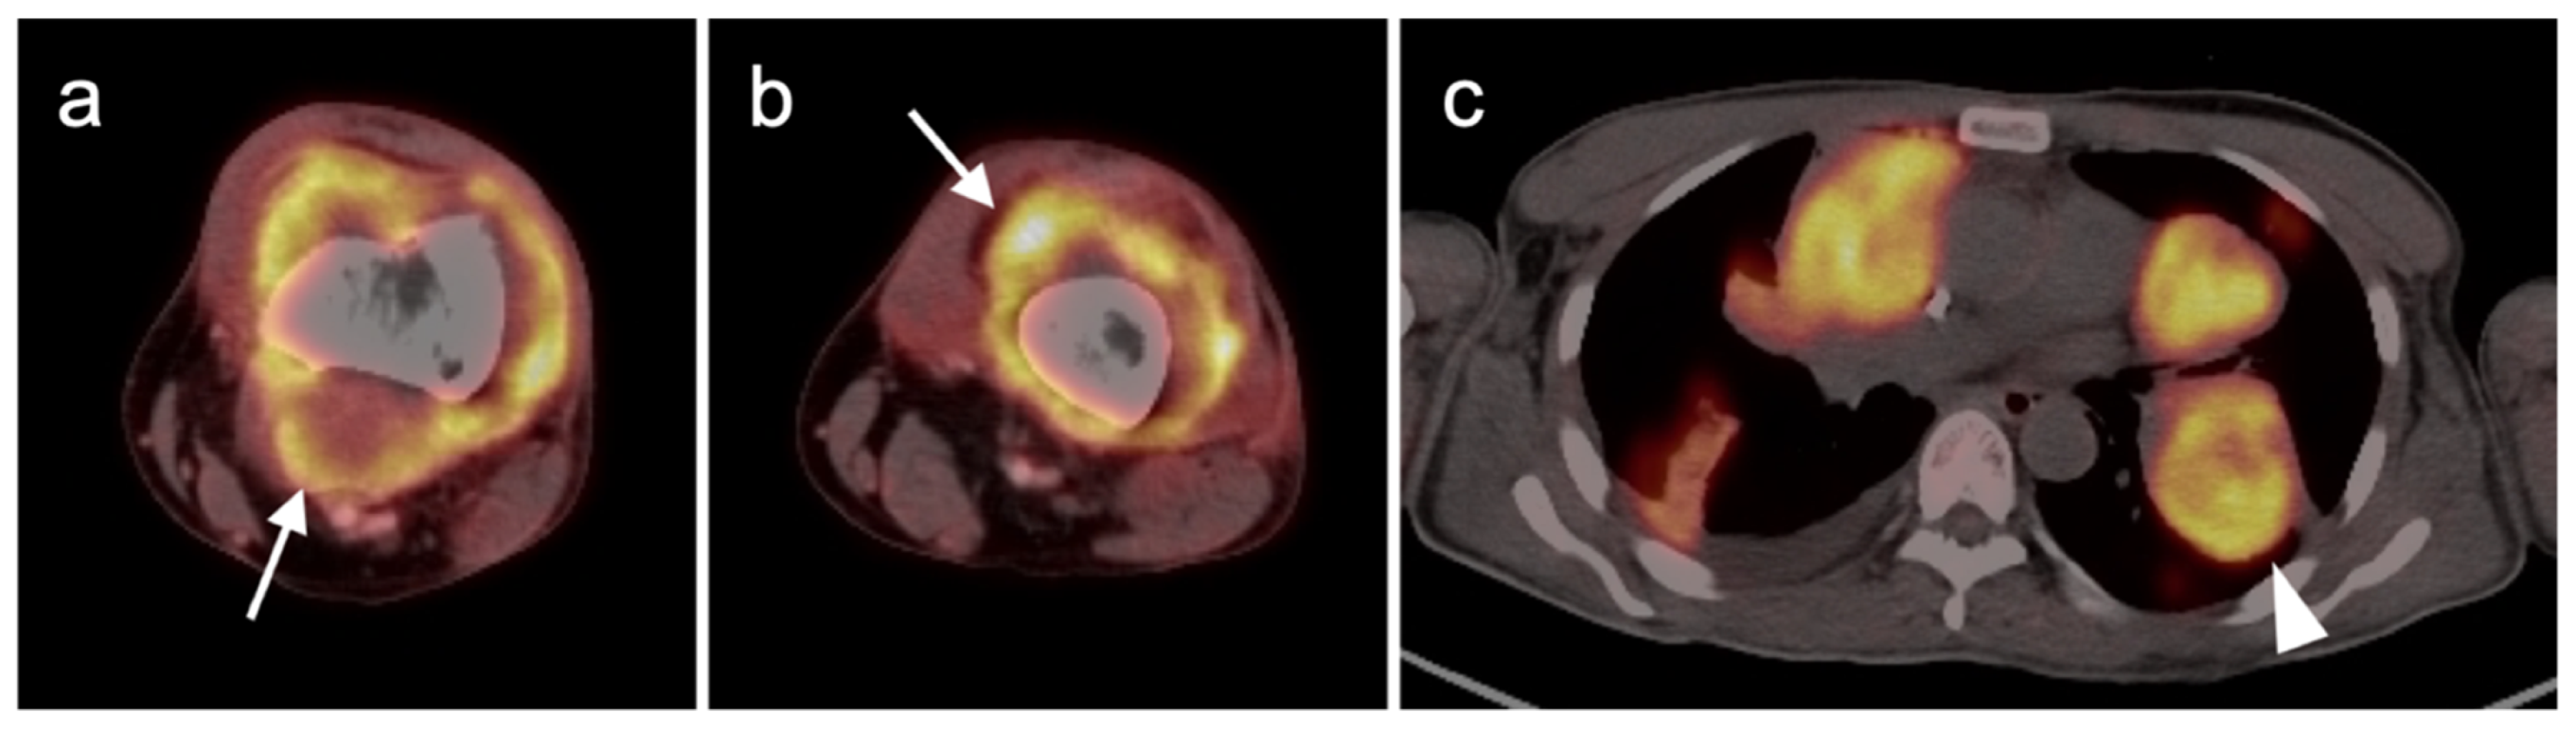

3.1.1. Undifferentiated Pleomorphic Sarcoma

3.1.2. Leiomyosarcoma

3.1.3. Angiosarcoma